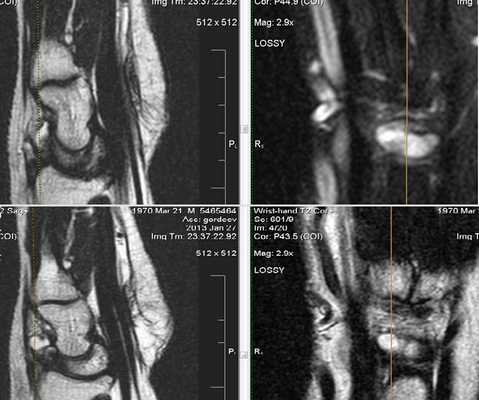

Липома сухожилия

Клинически: Отек левой руки, сохраняющийся длительное время, в настоящий момент пациент начал жаловаться на нарушение чувствительности боковых трех пальцев.

Капсулированная масса прикреплена к сухожилиям поверхностного и глубокого сгибателей указательного пальца. Липома из сухожилия (гистологически доказано).